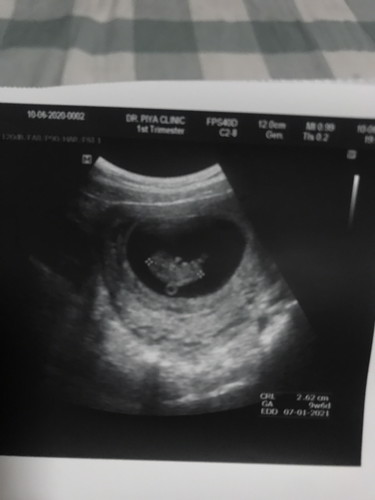

คุณแม่ท่านไหนท้อง9-10สัปดาห์รบกวนโชว์ผลอันเตอร์ซาวด์ของน้องหน่อยจ้า

พอดีวันนี้เราไปซาวด์มาเราเลยตื่นเต้นนิดนึงว่าน้องที่เราซาวด์ปกติดีไหมเพราะเราเคยแท้งมาแล้ว3คนเราอยากมีลูกมากเราเลยอยากทราบว่าน้องๆอายุครรภ์เท่าๆกับเราจะมีขนาดตัวประมานไหน

ซาววันนี้เลยค่ะ 9week6วัน